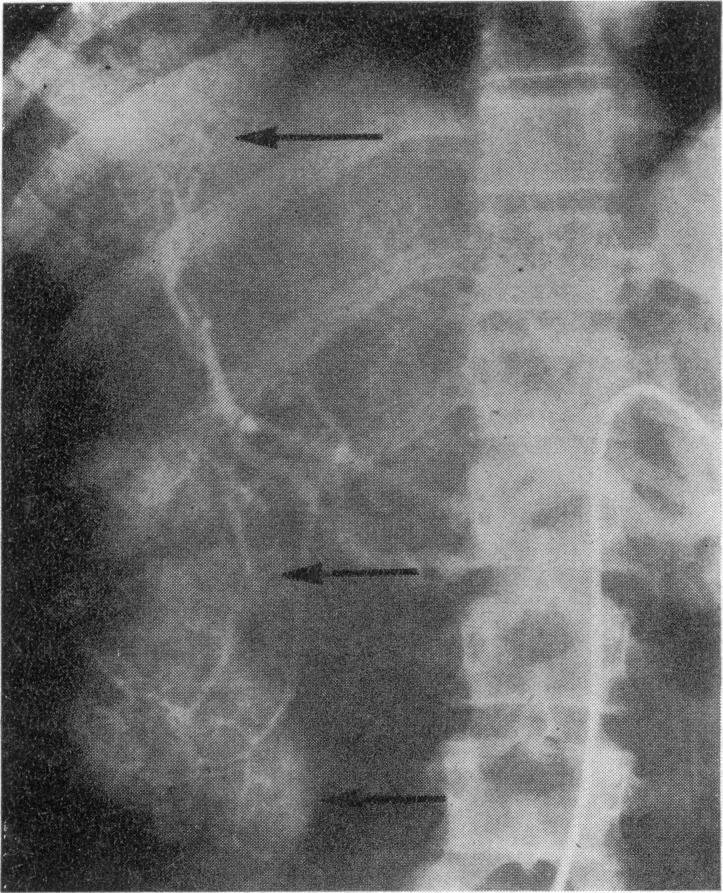

Angiography in the diagnosis of liver tumours.

Proc R Soc Med. 1974 Mar;67(3):208-11. doi: 10.1177/003591577406700317.